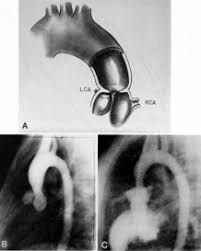

Supravalvular Aortic Stenosis Williams Syndrome Cardiac Case Studies Ctisus Ct Scanning

Contrast Enhanced Cardiac Computed Tomography Demonstrating Findings Of Download Scientific Diagram